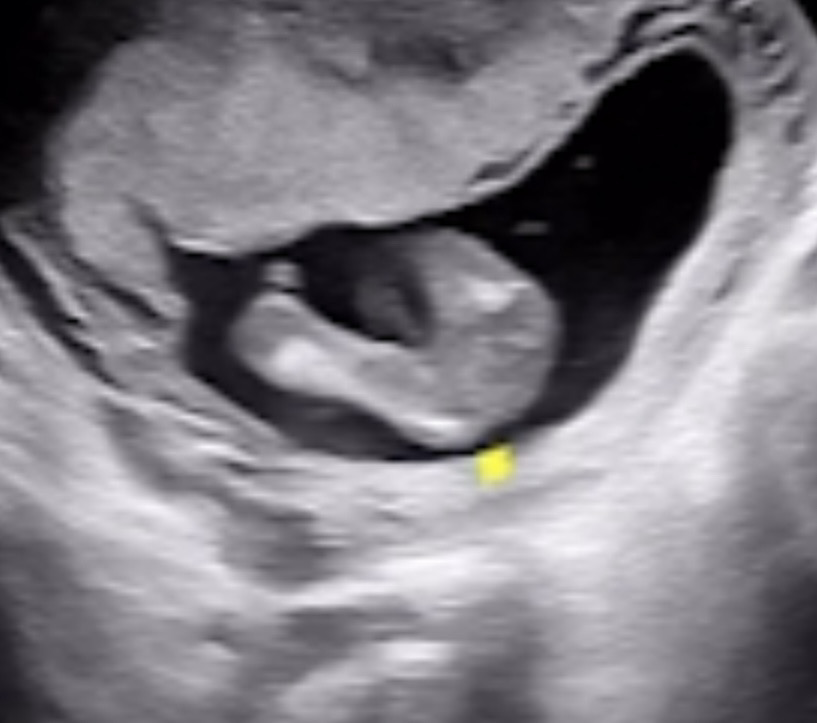

16주 차 ㅎㅎㅎㅎ반전없길🦋

장꾸맘님께선 12주랑 14주 모두 딸이라 하시고 16주에 병원가니 딸로 알고계세요~ 하시고 ㅎㅎ 첫째가 아들이랑 너무 행복하네용 반전없길!!!!!🙏🏼